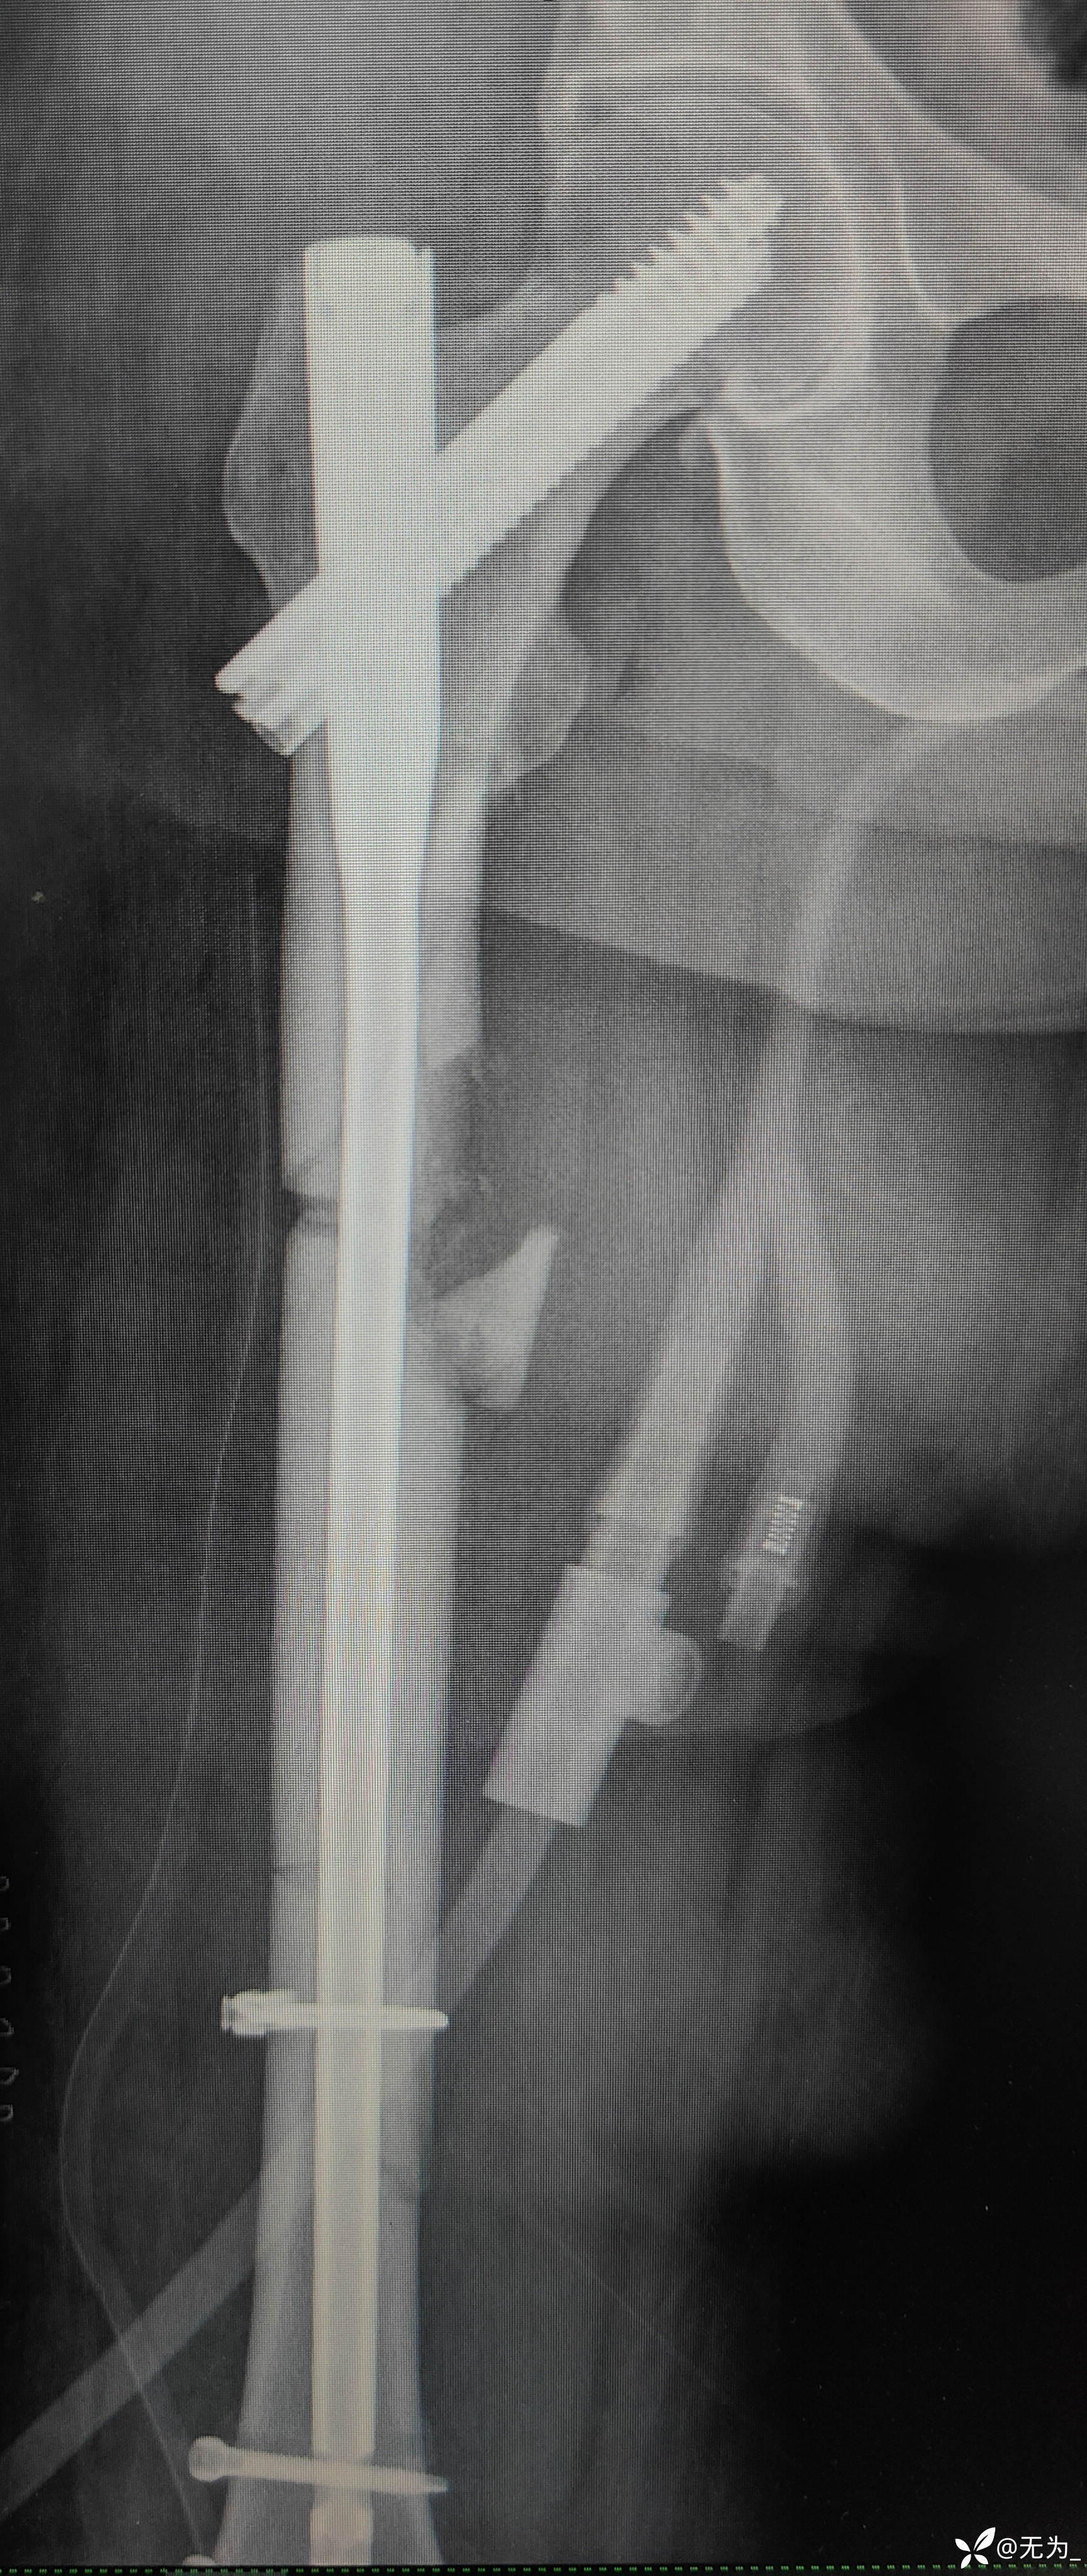

补液、输血后行头外伤缝合、大腿外架临时固定,转icu,病情逐渐稳定,3周后行右股骨外架拆除,复位内固定。

三段骨折,复位困难且时间长,患者取侧卧位,取大腿外侧切口,切开以后大量肉芽组织,清理折断,牵引复位,远折断钛揽固定,近折端钳夹复位,开孔、扩髓,置入髓内钉,螺钉固定,内侧骨块未处理伴骨缺损,未植骨避免感染。